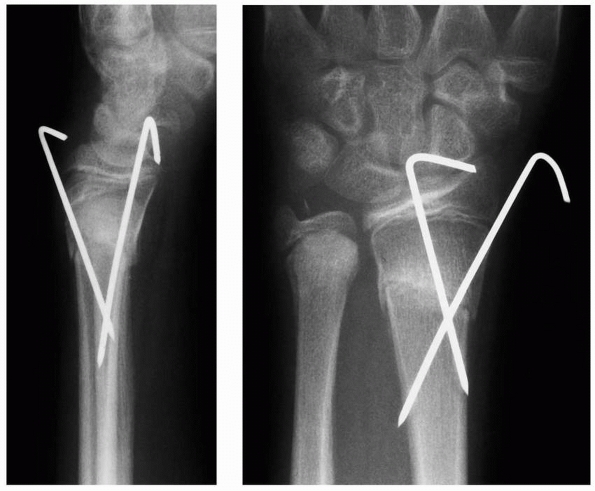

FIGURE 9-17 A.

Clinical photograph of patient with a displaced Salter-Harris type II fracture of the distal radius. The patient has marked swelling volarly with hematoma and fracture displacement. The patient had a median neuropathy upon presentation. B. Lateral radiograph of the displaced fracture. C. Lateral radiograph following closed reduction and cast application. Excessive flexion has been utilized to maintain fracture reduction, resulting in persistent median neuropathy and increasing pain. D. Radiographs following urgent closed reduction and percutaneous pinning. E. Follow-up radiograph depicting distal radial physeal arrest and increased ulnar variance. |